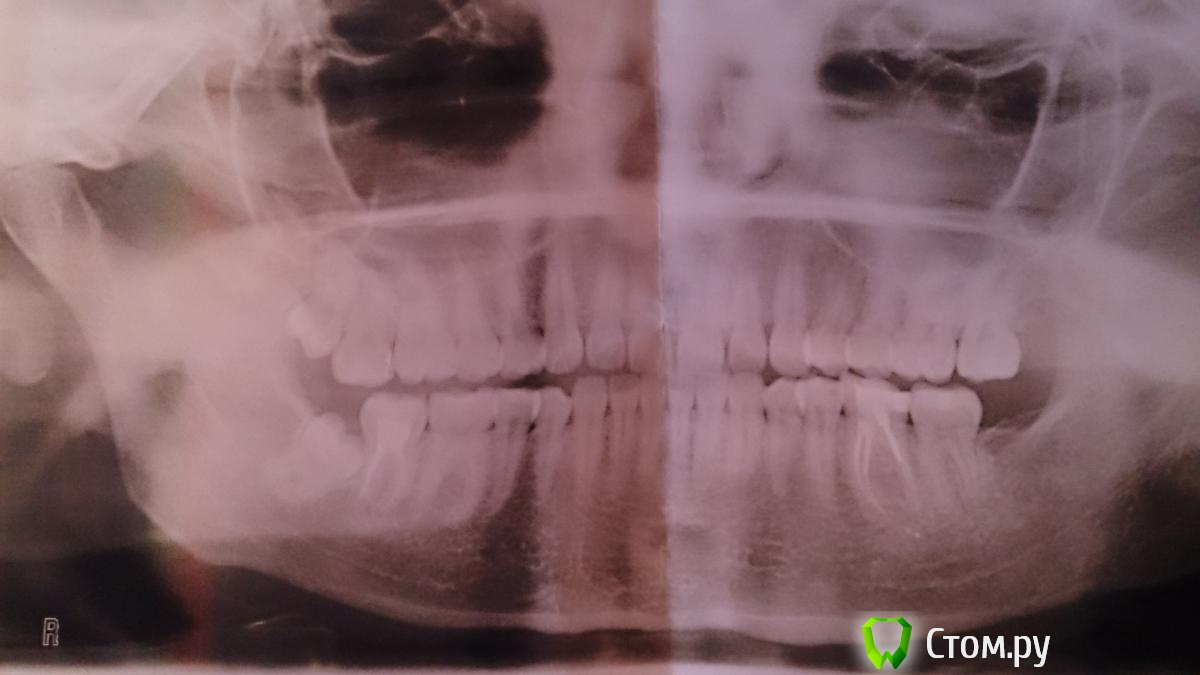

faity Опубликовано 25 июня, 2014 Поделиться Опубликовано 25 июня, 2014 снимок так себе, нужен более свежий в идеале я бы для удаления избрал бы другую тактику, вместо долото и киянки я бы распилил зуб, а потом зашил. травма по минимуму, дискомфорта для пациента никакого. 1 Ссылка на комментарий

Cresset Опубликовано 25 июня, 2014 Автор Поделиться Опубликовано 25 июня, 2014 снимок так себе, нужен более свежий в идеале я бы для удаления избрал бы другую тактику, вместо долото и киянки я бы распилил зуб, а потом зашил. травма по минимуму, дискомфорта для пациента никакого.Спасибо за ответ.Снимок недельной давности, за качество извиняюсь. Ссылка на комментарий

samsonov Опубликовано 25 июня, 2014 Поделиться Опубликовано 25 июня, 2014 Спасибо за ответ.Снимок недельной давности, за качество извиняюсь.Не сходятся Ваши данные со снимком что- то ... 1 Ссылка на комментарий

Cresset Опубликовано 25 июня, 2014 Автор Поделиться Опубликовано 25 июня, 2014 Не сходятся Ваши данные со снимком что- то ...Почему не сходятся?Снимок сделан 16.06.14, история про удаление нижней восьмерки - 2010 года.Вопрос возник в связи с предстоящим удалением второго нижнего (правого). Ссылка на комментарий

samsonov Опубликовано 25 июня, 2014 Поделиться Опубликовано 25 июня, 2014 Да,действительно мутный снимок. Пригляделся- сошлось.) Ссылка на комментарий